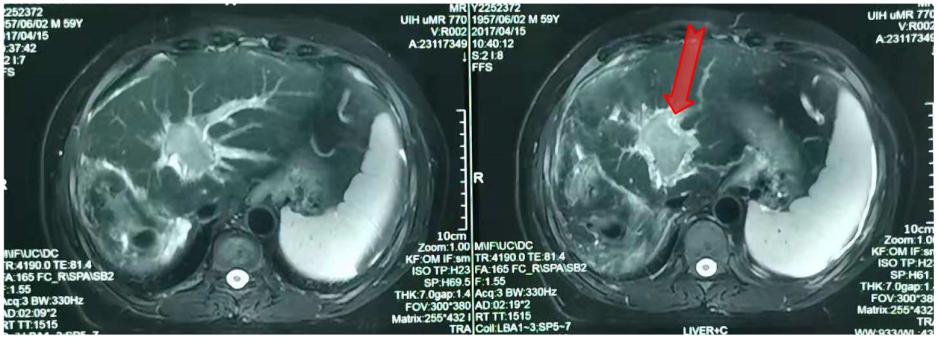

2017年4月15日复查,疾病进展(图3)。出现门腔静脉间淋巴结转移(图4)。

图3.术后7个月复查腹部MR

2017年5月再次行一次TACE治疗。6月行射波刀治疗,8 Gy/次,共6次。放疗后淋巴结及门静脉癌栓退缩,但是右肝又出现了新的病灶(图5)。

图5. 放疗后腹部MR